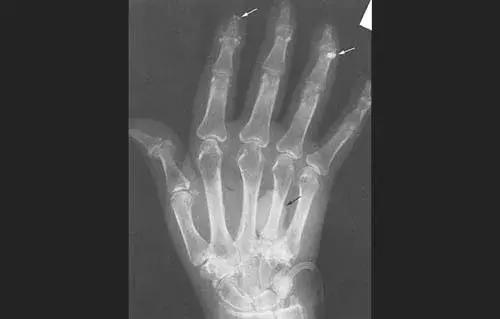

危及关节时,关节会被破坏,使关节慢慢畸形,譬如双手呈鸡爪状,一看便知功能尽失。

更加严重的时候,甚至还会瘫痪、骨骼破坏、肌肉萎缩,若是不及时治疗,所有内脏器官都逃不过灾厄。

类风湿导致手掌变形、关节钙化